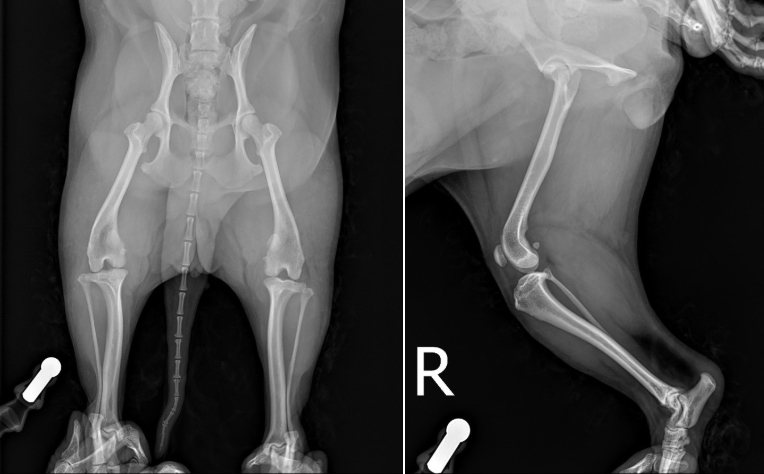

명란이는 오른쪽 뒷다리 파행이 2주 이상 지속되고 있었습니다. 타원에서 진통소염제를 처방받아 꾸준히 복약했음에도 호전이 없었습니다.

보행을 미끄럽지 않은 바닥에서 시켜봤을 시, 우측 다리를 완전히 들고 걸어다니고 있었으며, 신체검사상, 십자인대가 끊어졌을 때 양성을 보이는 검사 두가지에서 모두 양성 반응을 보였습니다.

엑스레이 상 십자인대가 끊어지면서 무릎이 앞으로 밀리는 소견이 확인되었습니다.

또한 십자인대가 끊어지게 되면 급성 관절염 및 부종 소견이 동반될 수 있는데 그 또한 확인되어 종합적으로 봤을 때, 환자는 우측 십자인대 완전 단열로 인해 이미 관절염도 진행되고 있고 통증이 있는 것으로 고려되었습니다.

TPLO 수술을 계획하기 위해서는 엑스레이 촬영 했을 때 좌측에 보이는 calibration ball 을 같이 포함하여 촬영을 해야합니다. ▼

* 관절내 부종이 확인됩니다.

* 무릎을 굽힌 상태로 엑스레이 촬영 시 십자인대 단열로 인해 무릎이 앞으로 전방변위되는 것이 확인됩니다.